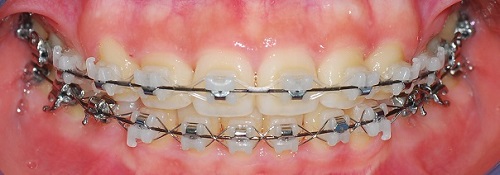

치과쌤이 치아를 쭉보시고 와이어를 얇은것으로 바꿔주셧어요.

드뎌드뎌 치아교정 마무리 작업에 슬슬 들어가는군용!

발치 공간은 다 닫혓어요. ^__________^

(정면사진)

측면에서도 치아 사이에 구멍은 보이지 않아요!